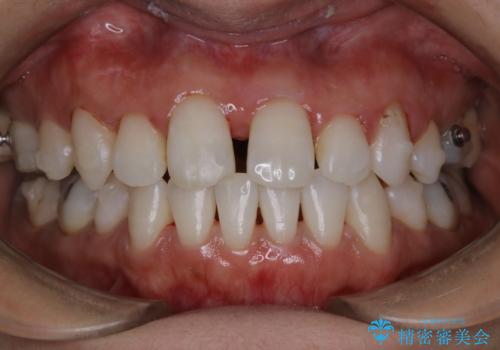

インビザラインでの矯正治療でアタッチメントset前のPMTC